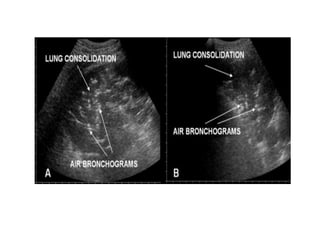

Tissue pattern representative of Alveolar

Consolidation

Presence of hyperechoic punctiform

imagesrepresentative of air bronchograms

Tissue pattern representativeof Alveolar Consolidation Presence of hyperechoic punctiform imagesrepresentative of air bronchograms Pleural effusion Lower lobe